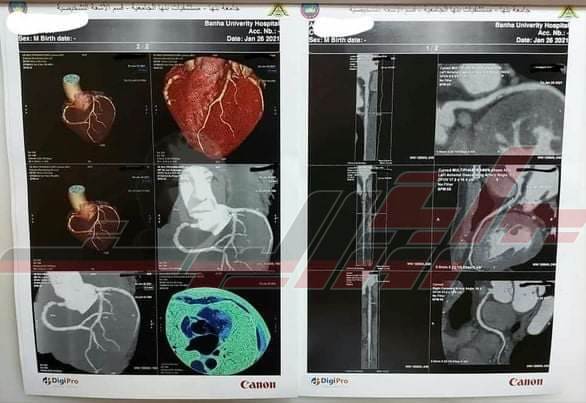

بدء تشغيل أول جهاز أشعة مقطعية للشرايين التاجية والأوعية الدموية ببنها الجامعى

أعلن مستشفى بنها الجامعي بدء تشغيل جهاز الأشعة المقطعية متعدد المقاطع الجديد 128 الخاص بالشرايين التاجية والأوعية الدموية لخدمة القليوبية والمحافظات المجاورة.

وقال الدكتور عمرو الدخاخني إلى أن هذا الإنجاز يأتي تزامنًا مع خطه الدولة 2030 للقضاء على قوائم الإنتظار الخاصة بعمليات القلب والقسطرة، مشيرًا إلى أن هذا الجهاز يساعد على اكتشاف وتشخيص العيوب الخلقية بالقلب وأفضل من القسطرة فى بعض الحالات.